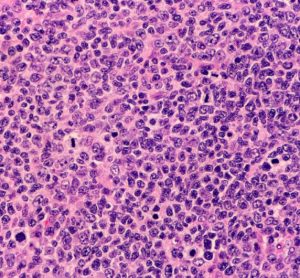

GSK immuno-oncology treatment achieves novel EU approval

The EC’s approval of the immuno-oncology treatment “will define a new standard of care for certain patients with advanced or recurrent endometrial cancer in the EU,” says principal investigator of the RUBY trial.